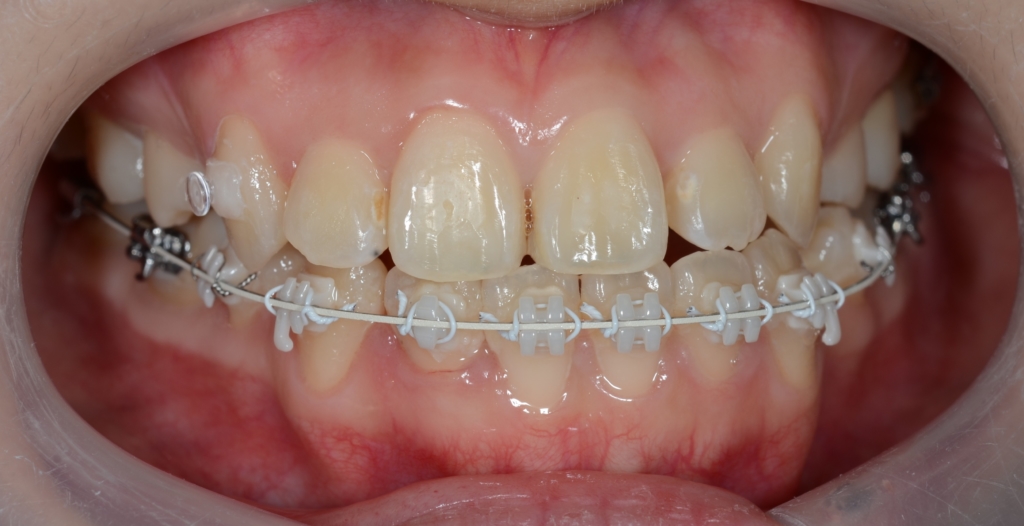

【1年経過】

【残る隙間を閉じて仕上げへ】

【After】

「もう十分です、早く外して欲しい!」という患者さんの声に甘えて治療を終えることにしました